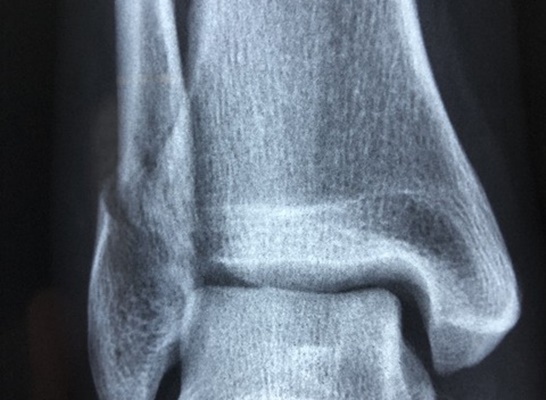

발목 관절염에는 여러 가지 증상이 있습니다요. 걸을 때마다 통증이 반복되거나 발목 관절이 붓는 것, 발목 관절이 원활하게 움직이기 어려운 것 모두 발목 관절염 증상에 해당 됩니다. 또한 발목 앞쪽에 통증이 반복되고 열감이나 부종 동반 되기도 합니다.

다양한 발목 관절염 증상이 나타나면 초기에 물리치료나 주사 치료, 약 처방 등을 통해서 치료를 진행하게 됩니다. 하지만 증상이 심하고 초기 치료에 실패하게 되면 중장기 관절염으로 판단하고 수술적 요법을 사용하여 치료해야 합니다. 중증 발목 관절염 치료는 인공 관절을 대체하는 수술로 조치 되기도 합니다.